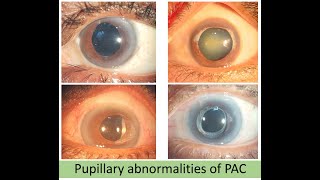

BIONIKO OKULO Advanced Anterior Segment Model - Cataract and its Complications Pupilloplasty in Primary Angle Closure(PAC) with Complete Pupillary Paralysis

Pupilloplasty in Primary Angle Closure(PAC) with Complete Pupillary Paralysis

BIONIKO OKULO Advanced Anterior Segment Model - Cataract and its Complications Pupilloplasty in Primary Angle Closure(PAC) with Complete Pupillary Paralysis

Pupilloplasty in Primary Angle Closure(PAC) with Complete Pupillary Paralysis